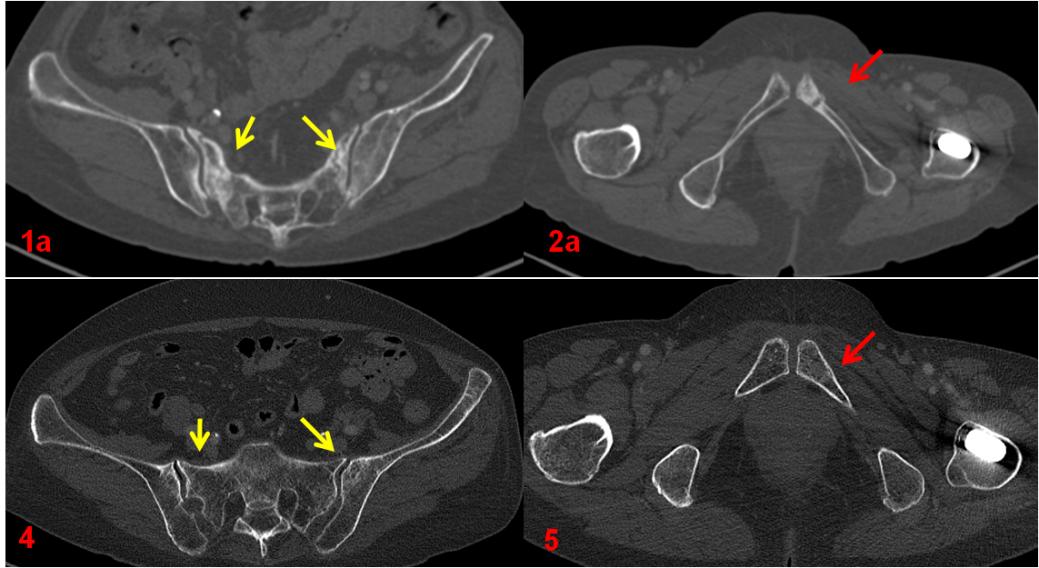

復(fù)查CT(圖4、5)對比前片(圖1a、2a)。前片所示骶骨密度不均勻增高(1a,黃箭),本次明顯恢復(fù)(4,黃箭),左側(cè)恥骨骨質(zhì)斷裂(2a,紅箭),本次基本消失(5,紅箭)。